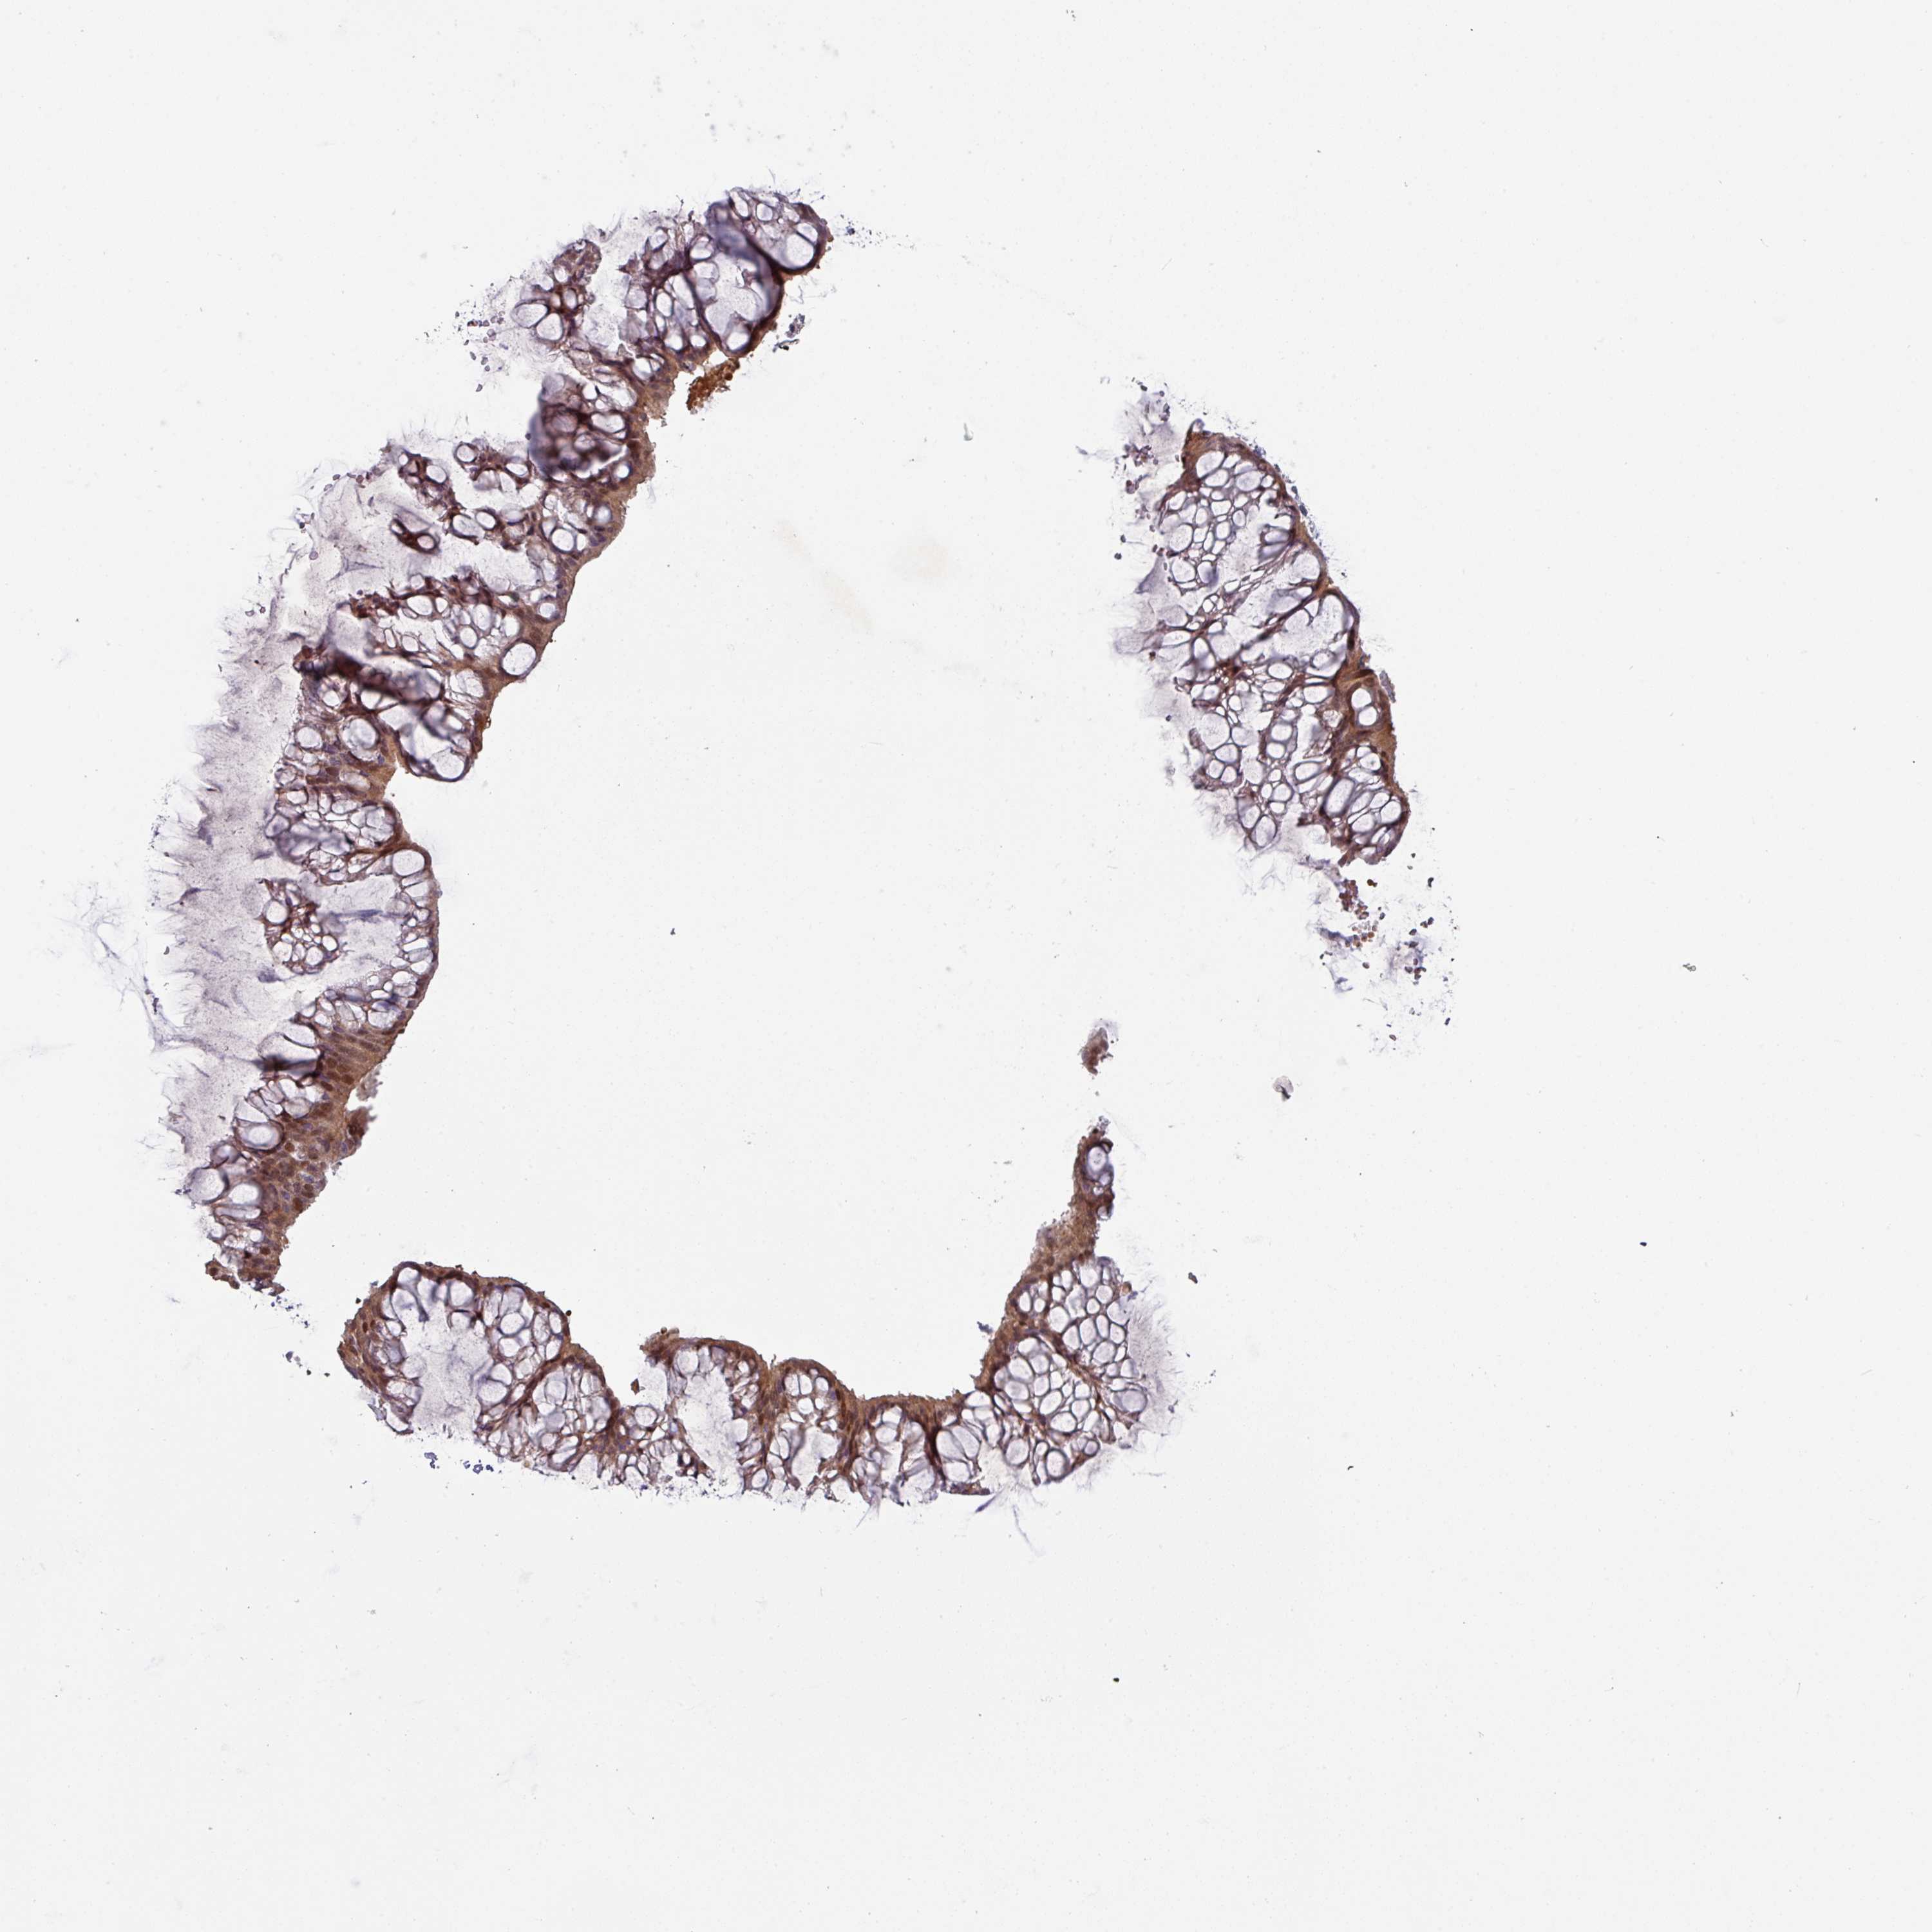

OVARIAN CANCER - Protein expressioni

A mouse-over function shows sample information and annotation data. Click on an image to view it in a full screen mode. Samples can be filtered based on level of antibody staining by selecting one or several of the following categories: high, medium, low and not detected. The assay and annotation is described here.

Note that samples used for immunohistochemistry by the Human Protein Atlas do not correspond to samples in the TCGA dataset.

Antibody stainingi

Antibody staining in the annotated cell types in the current human tissue is reported as not detected, low, medium, or high, based on conventional immunohistochemistry profiling in selected tissues. This score is based on the combination of the staining intensity and fraction of stained cells.

Each image is clickable and will lead to virtual microscopy that enables deeper exploration of all samples and also displays staining intensity scores, fraction scores and subcellular localization as well as patient and tissue information for each sample.

Antibody HPA052014

Staining

High

Medium

Low

Not detected

Intensity

Strong

Moderate

Weak

Negative

Quantity

>75%

75%-25%

<25%

None

Location

Nuclear

Cytoplasmic/membranous

Cytoplasmic/membranous,nuclear

Cystadenocarcinoma, serous, NOS

Carcinoma, NOS

Cystadenocarcinoma, mucinous, NOS

Carcinoma, endometroid